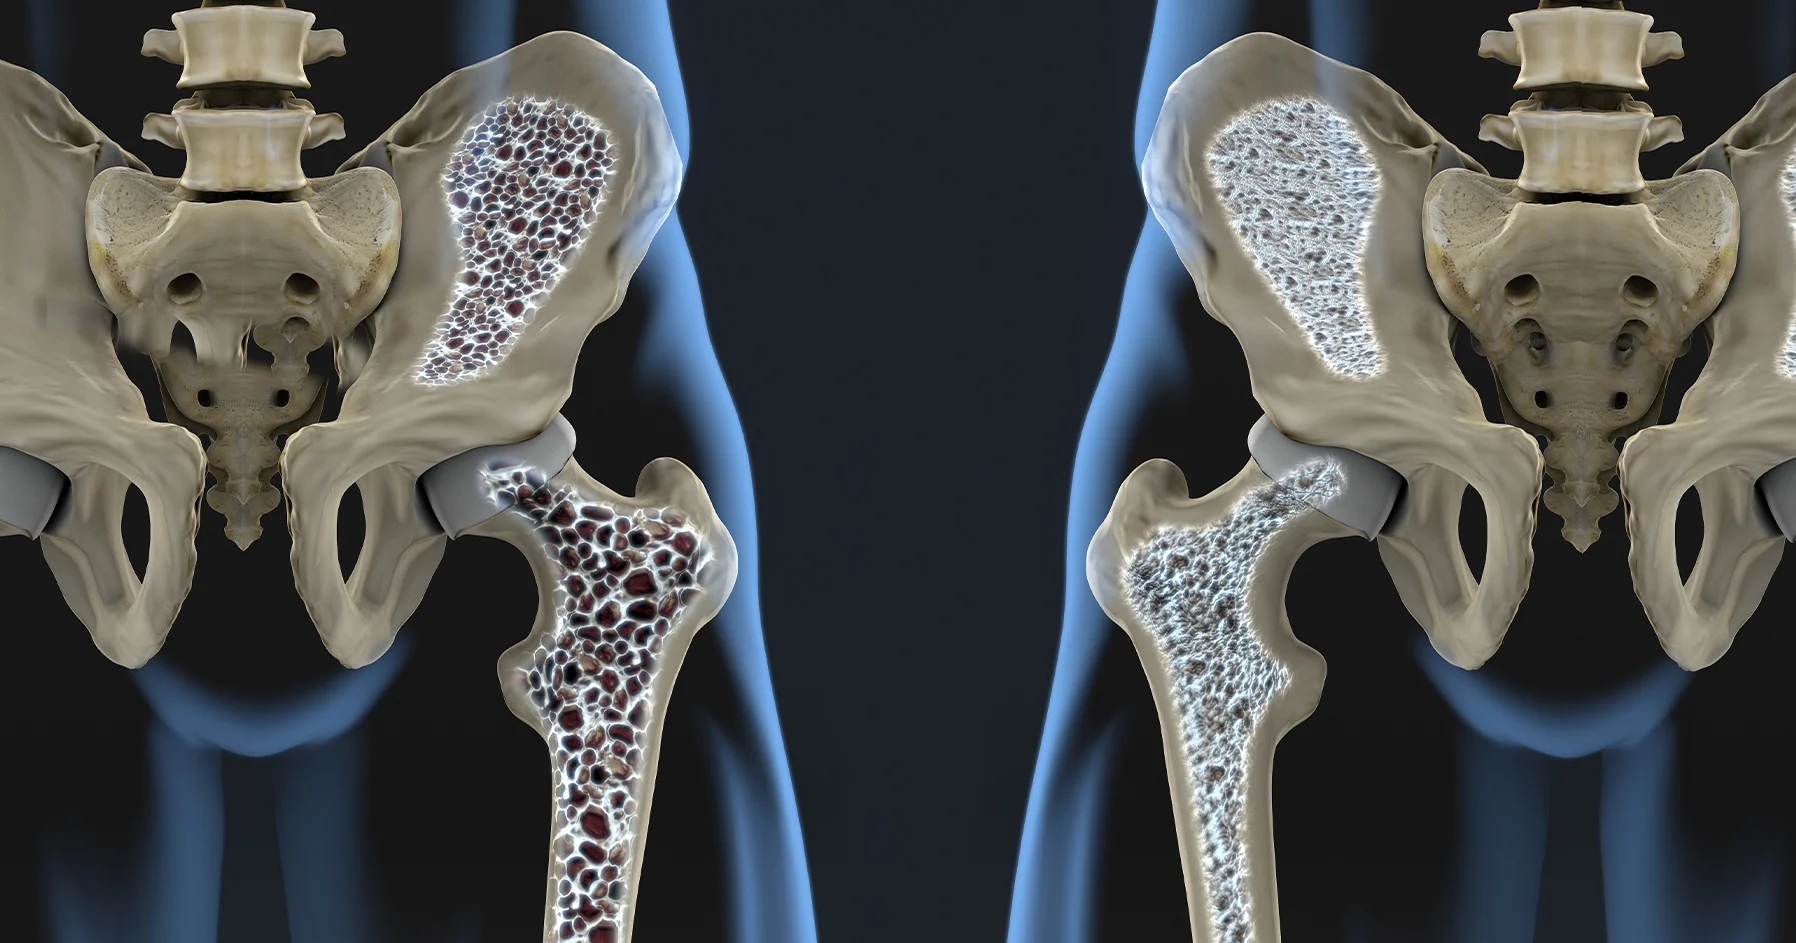

Osteoporoza, caracterizată prin scăderea densității osoase și creșterea fragilității oaselor, este o problemă de sănătate publică majoră, afectând în special persoanele în vârstă. Tratamentele actuale se concentrează, în principal, pe încetinirea progresiei bolii și pe reducerea riscului de fracturi. Noua descoperire deschide însă o perspectivă promițătoare, sugerând posibilitatea regenerării osoase și, implicit, a vindecării. Receptorul GPR133, anterior puțin studiat, s-a dovedit a fi un punct cheie în acest proces.

nnÎn cadrul experimentelor, activarea GPR133 a stimulat mecanismele naturale de formare a oaselor, conducând la o creștere semnificativă a densității osoase. Mai mult, cercetătorii au observat și o refacere a țesutului osos deteriorat, ceea ce sugerează un potențial terapeutic extraordinar pentru pacienții cu osteoporoză. Rezultatele preliminare sunt extrem de încurajatoare și indică faptul că acest receptor ar putea fi o țintă eficientă pentru noi tratamente. Următorul pas este de a înțelege exact mecanismele prin care GPR133 influențează sănătatea oaselor.